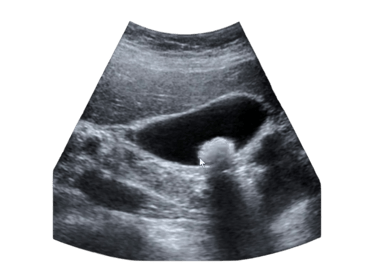

O diagnóstico costuma ser realizado por meio de ultrassonografia abdominal, um exame simples, indolor e altamente eficaz para detectar cálculos na vesícula. Em casos mais complexos, exames como tomografia ou ressonância magnética podem ser necessários.

O Ultrassom de abdome é o exame mais realizado para diagnósticar cálculos na vesícula biliar